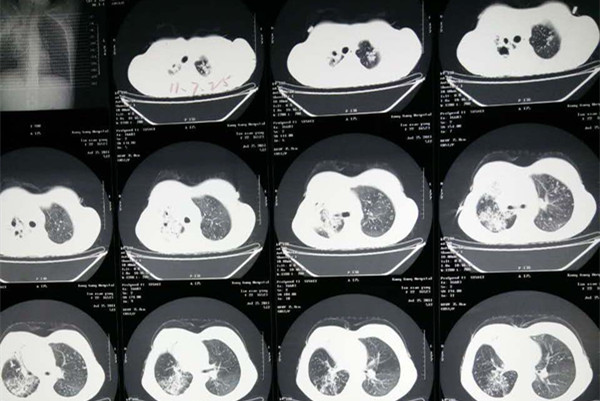

肺结核是由于患者肺部受到病菌感染而导致的一种慢性传染性疾病,虽然现在抗结核药物的出现让肺结核的治愈率明显提高,但是由于很多患者不规范的治疗导致治愈后,肺结核又出现复发的情况。那么肺结核复发怎么治呢?